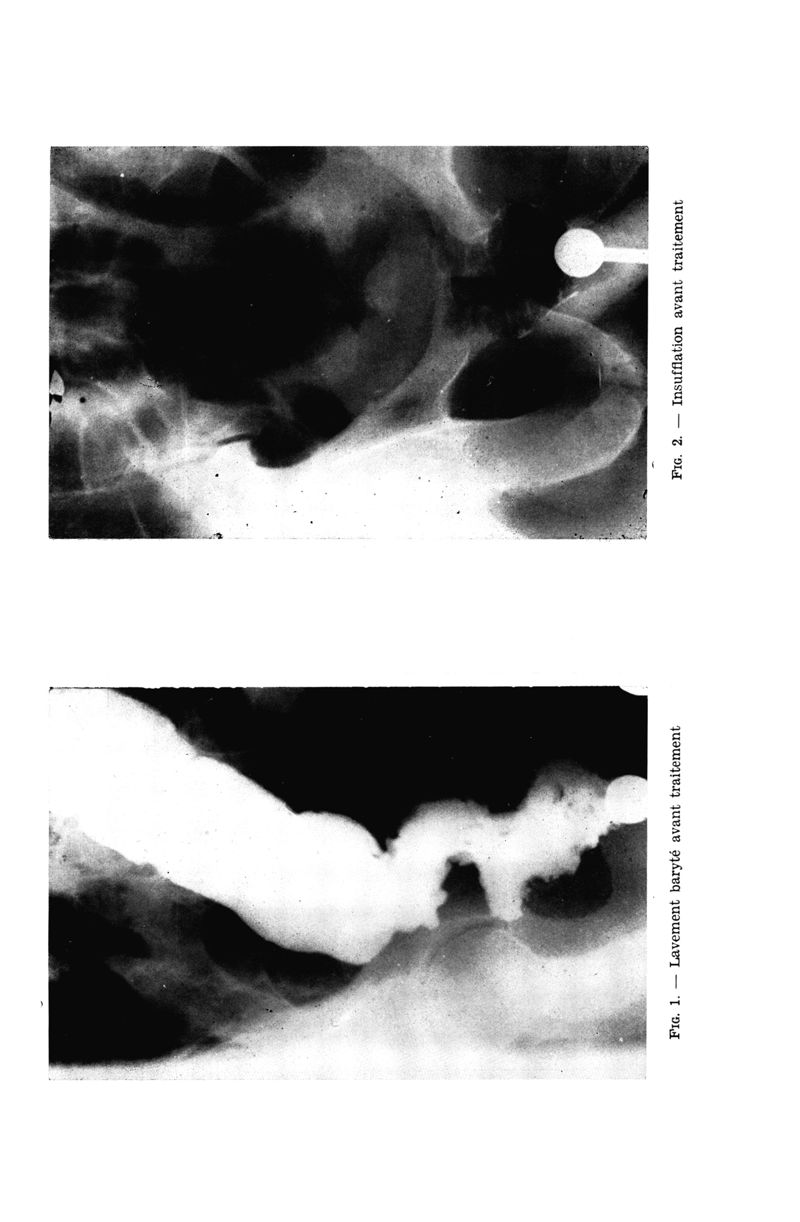

Médecine tropicale : Revue du corps de santé colonial

. - Marseille : Ecole d'application du service de santé des troupes coloniales, 1955.